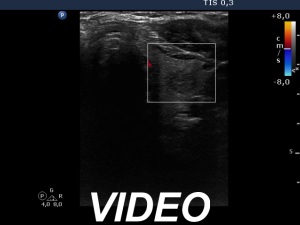

Comments. It is worth viewing the video to learn how to define the degree of substernal spread on ultrasound.